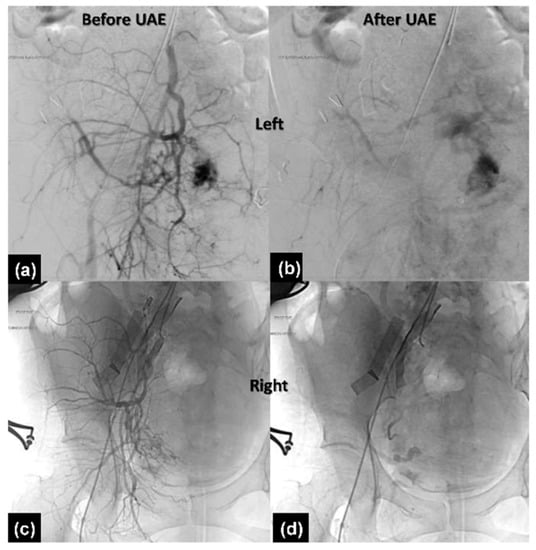

2.2.3. Therapeutic Intervention

2.2.4. Follow-Up and Outcomes